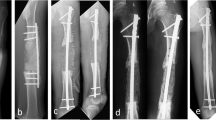

Plates or intramedullary nails were used to fix the defect end according to different bone defect sites and intramedullary infection. The broken end of the defect was filled with polymethyl methacrylate (PMMA) bone cement containing gentamicin. Subsequently, 2 g of antibiotic (vancomycin or imipenem) powder was added to 40 g cement powder, fully crushed, stirred evenly, and then mixed well with the liquid monomer. When the mixed antibiotic bone cement was in the dough stage, the bone defect was filled, the internal fixation plate or intramedullary nail was wrapped and extended 5–6 cm to the proximal and distal ends of the bone defect, and the bone cement was smoothed. When the bone cement solidified and heated up, ice-cold saline was used for flushing to reduce thermal damage to surrounding tissues. A typical case is shown in Fig. 1.

A infected limb with sinus and external fixator before the surgery. B X-ray of infected femoral bone before the surgery. C After a thorough debridement, antibiotic bone cement–coated nail and plate were used to stabilize the bone fracture, and the bone defect was filled with antibiotic cement spacer. From left to right: bone cement–coated K-wire was placed in the femoral medullary cavity. The steel plate was attached to the outside for reinforcement. D X-ray of the mid and lower level of the femoral cavity during the surgery. E, F Pictures after stage I surgery. G, H Autologous iliac bone graft combined with calcium sulfate and calcium phosphate composite materials filled into the bone defect cavity. I, J Post-operative X-ray and the incision healed at the 3-month follow-up

With the help of intraoperative fluoroscopy, external fixation instruments were used to stabilize the bone defect. The proximal and distal fixation pins were kept away from the infected area, and the important blood vessels and nerves were avoided during needle insertion. The broken end of the defect was also filled with the mixed antibiotic bone cement.